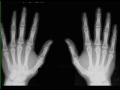

Normal Hands on X-ray

Normal x-ray of the hands. No evidence of fracture dislocation. The joint spaces appear normal. No evidence of arthritis.